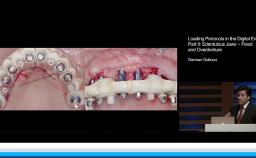

German Gallucci

Boston, United States